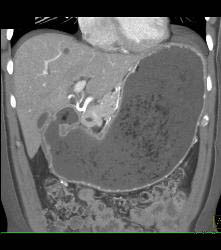

Antral Carcinoma- See Sequence